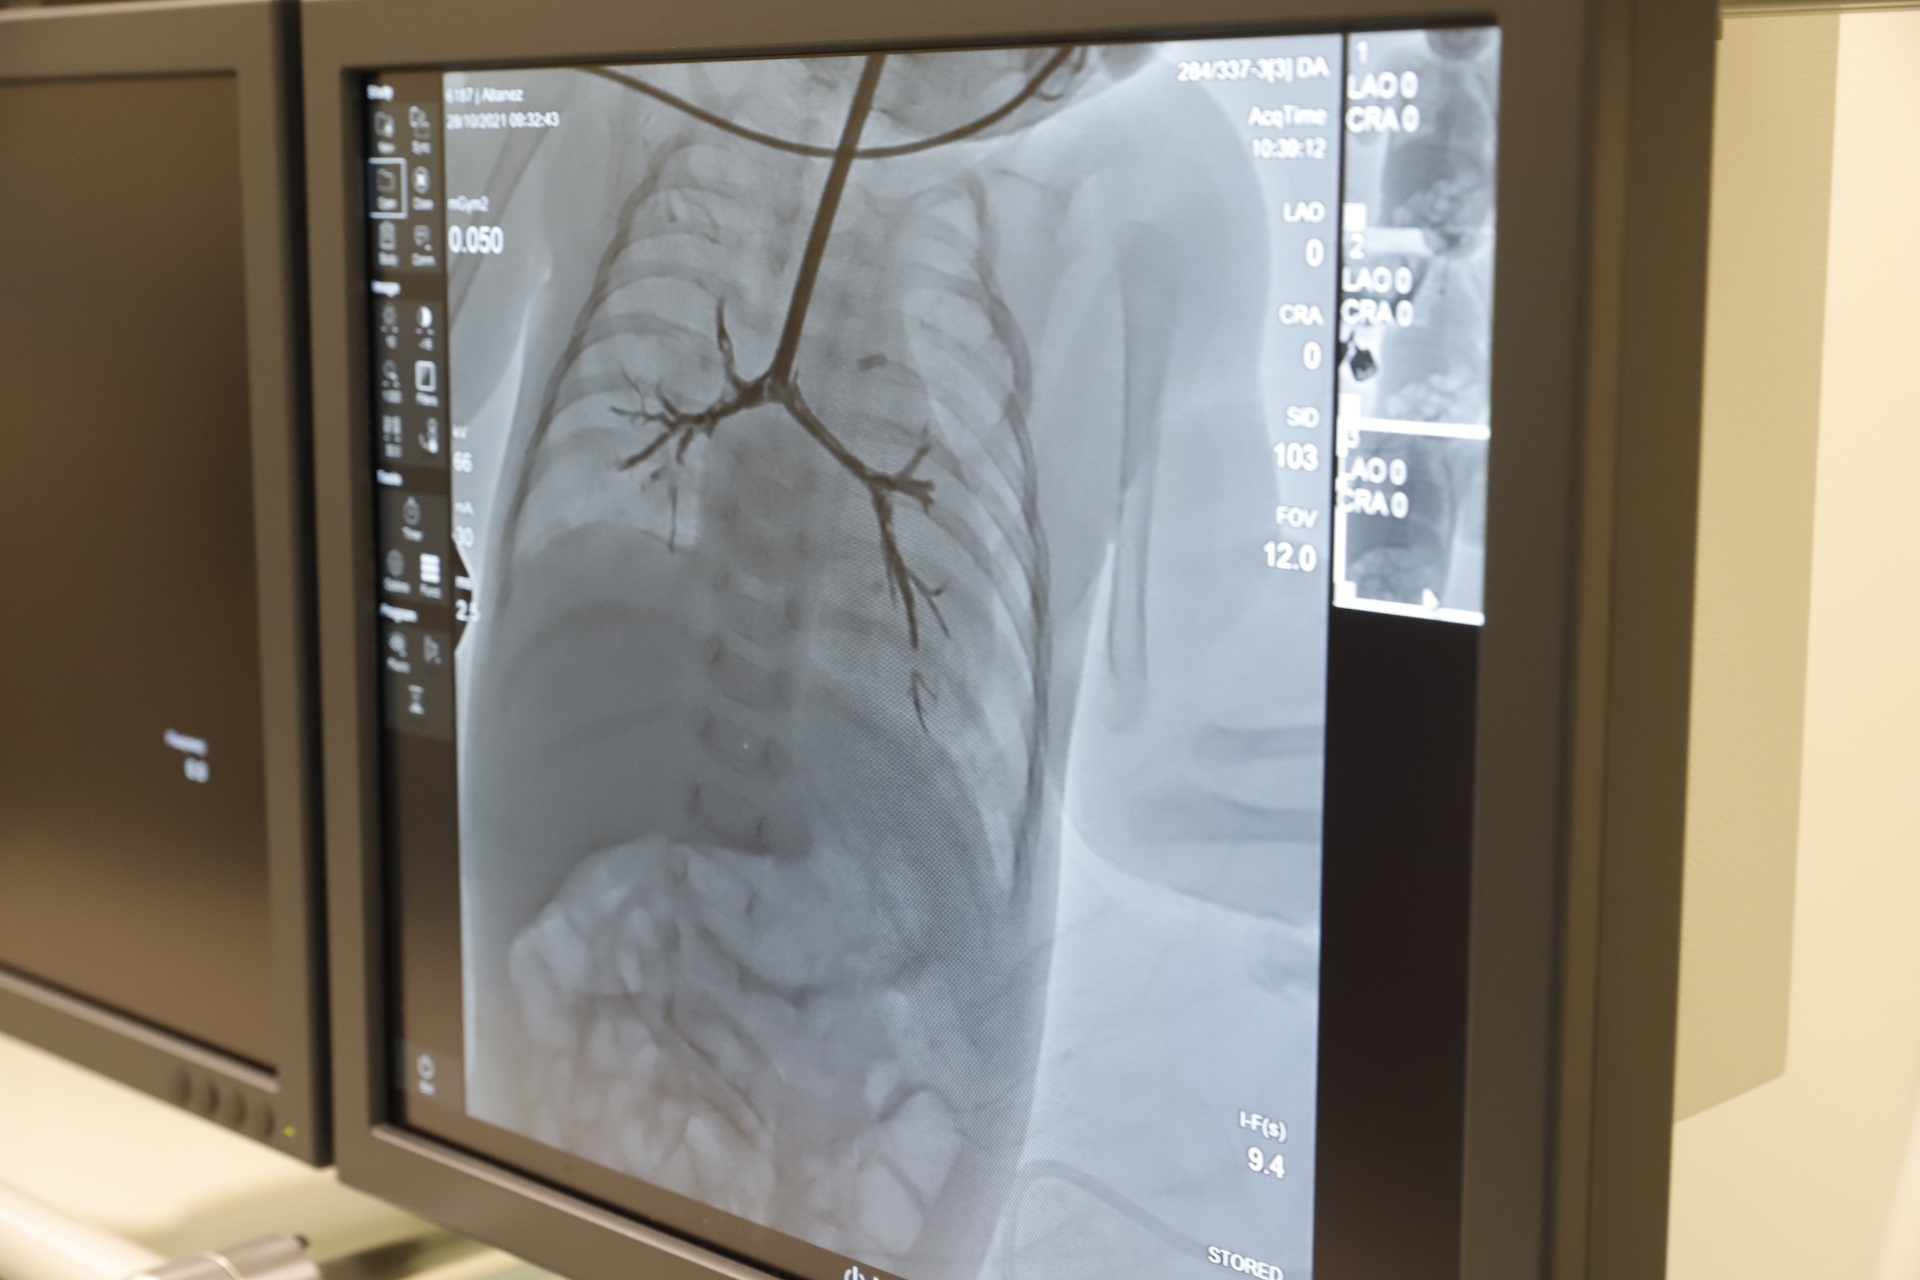

У Дніпрі лікарі міської багатопрофільної клінічної лікарні матері та дитини ім. проф. М. Ф. Руднєва провели унікальну операцію на відкритому серці двомісячному немовляті зі складною патологією – вадою серця та вродженим стенозом трахеї. Для радикального втручання серце зупиняли на 38 хвилин. Дитина дихала за допомогою штучного кровообігу.

«Для стабілізації стану дитини провели перший етап лікування – закриття артеріального протоку. Використовуючи досвід наших європейських партнерів, провели балонну дилатацію трахеї для радикальної корекції вади серця в умовах штучного кровообігу. Це робили на зупиненому на 38 хвилин серці. Вдячні нашим колегам, команді кардіохірургів з Інституту серця МОЗ України, які теж брали участь в операції. Наразі стан дитини – стабільний. Дівчинка переведена з реанімації до відділення патології новонароджених. Досвід саме такої операції мали вперше», – розповів під час пресконференції заступник медичного директора міської багатопрофільної клінічної лікарні матері та дитини ім. проф. М. Ф. Руднєва Олександр Романенко.

За словами завідувача кардіохірургічного відділення згаданої лікарні Павла Павлова, завдяки проведеній операції дитина може самостійно дихати і має усі шанси на подальше здорове життя.

«На апараті штучної вентиляції дитина перебувала упродовж трьох тижнів. Під час операції усунули усі внутрішньосерцеві вади. А завдяки процедурі балонній дилатації усунули патологію трахеї. Коли три дні тому прибирали трубочку у дитини, був такий бентежливий момент, бо не знали чи зможе вона повноцінно самостійно дихати. Те, що ми зараз спостерігаємо, – наші зусилля увінчалися успіхом. Це дуже радує. Дитина самостійно дихає без усіляких підтримок. Звісно, провести таку операцію вдалось завдяки сучасному обладнанню, яке маємо у лікарні», – додав Павло Павлов.